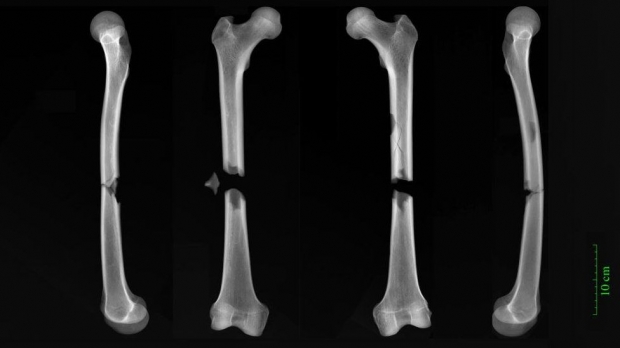

영국 일간 가디언 26일자 보도에 따르면, 케임브리지대 연구진이 1100년대부터 1530년대까지 케임브리지 내 세 무덤에서 발굴한 12세 이상 중세인 314명의 유골을 분석해 골절흔은 교구 공동묘지에 묻힌 하층민 사이에서 흔했다는 것을 알아냈다. 반면 아우구스티누스 수도원에 묻힌 상류층 성직자들 사이에서도 이런 부상을 입었다는 증거가 나와 이들 역시 폭력적인 사건으로부터는 보호받지 못했다는 점을 시사했다.

연구진은 이 연구에서 교구 공동묘지에 묻힌 사람들에게서 골절이 가장 흔하게 일어났었다는 것을 발견했다. 이곳의 유골 중 44%에게서 골절 징후를 발견, 이는 수도원에 묻힌 사람들 중 32%에게서 이런 징후가 나타난 것보다 많은 것이다.

이 연구에서는 또 이런 골절상이 남성들 사이에서 더 흔했지만 일부 여성도 이런 징후를 보인 것을 발견했다. 디트마 박사는 “한 가난한 여성은 삶의 어느 시점에서 턱뼈가 부러져 치유됐지만, 갈비뼈와 발뼈가 부러진 것을 포함해 다른 부위에도 많은 부상을 입었다”고 말했다. 이어 “턱뼈가 부러진 것은 넘어져서 생긴 것일 수 있지만, 다른 가능성도 있다”면서 “오늘날 여성들은 가정 폭력의 결과로 턱뼈 골절을 겪기도 한다”고 덧붙였다.